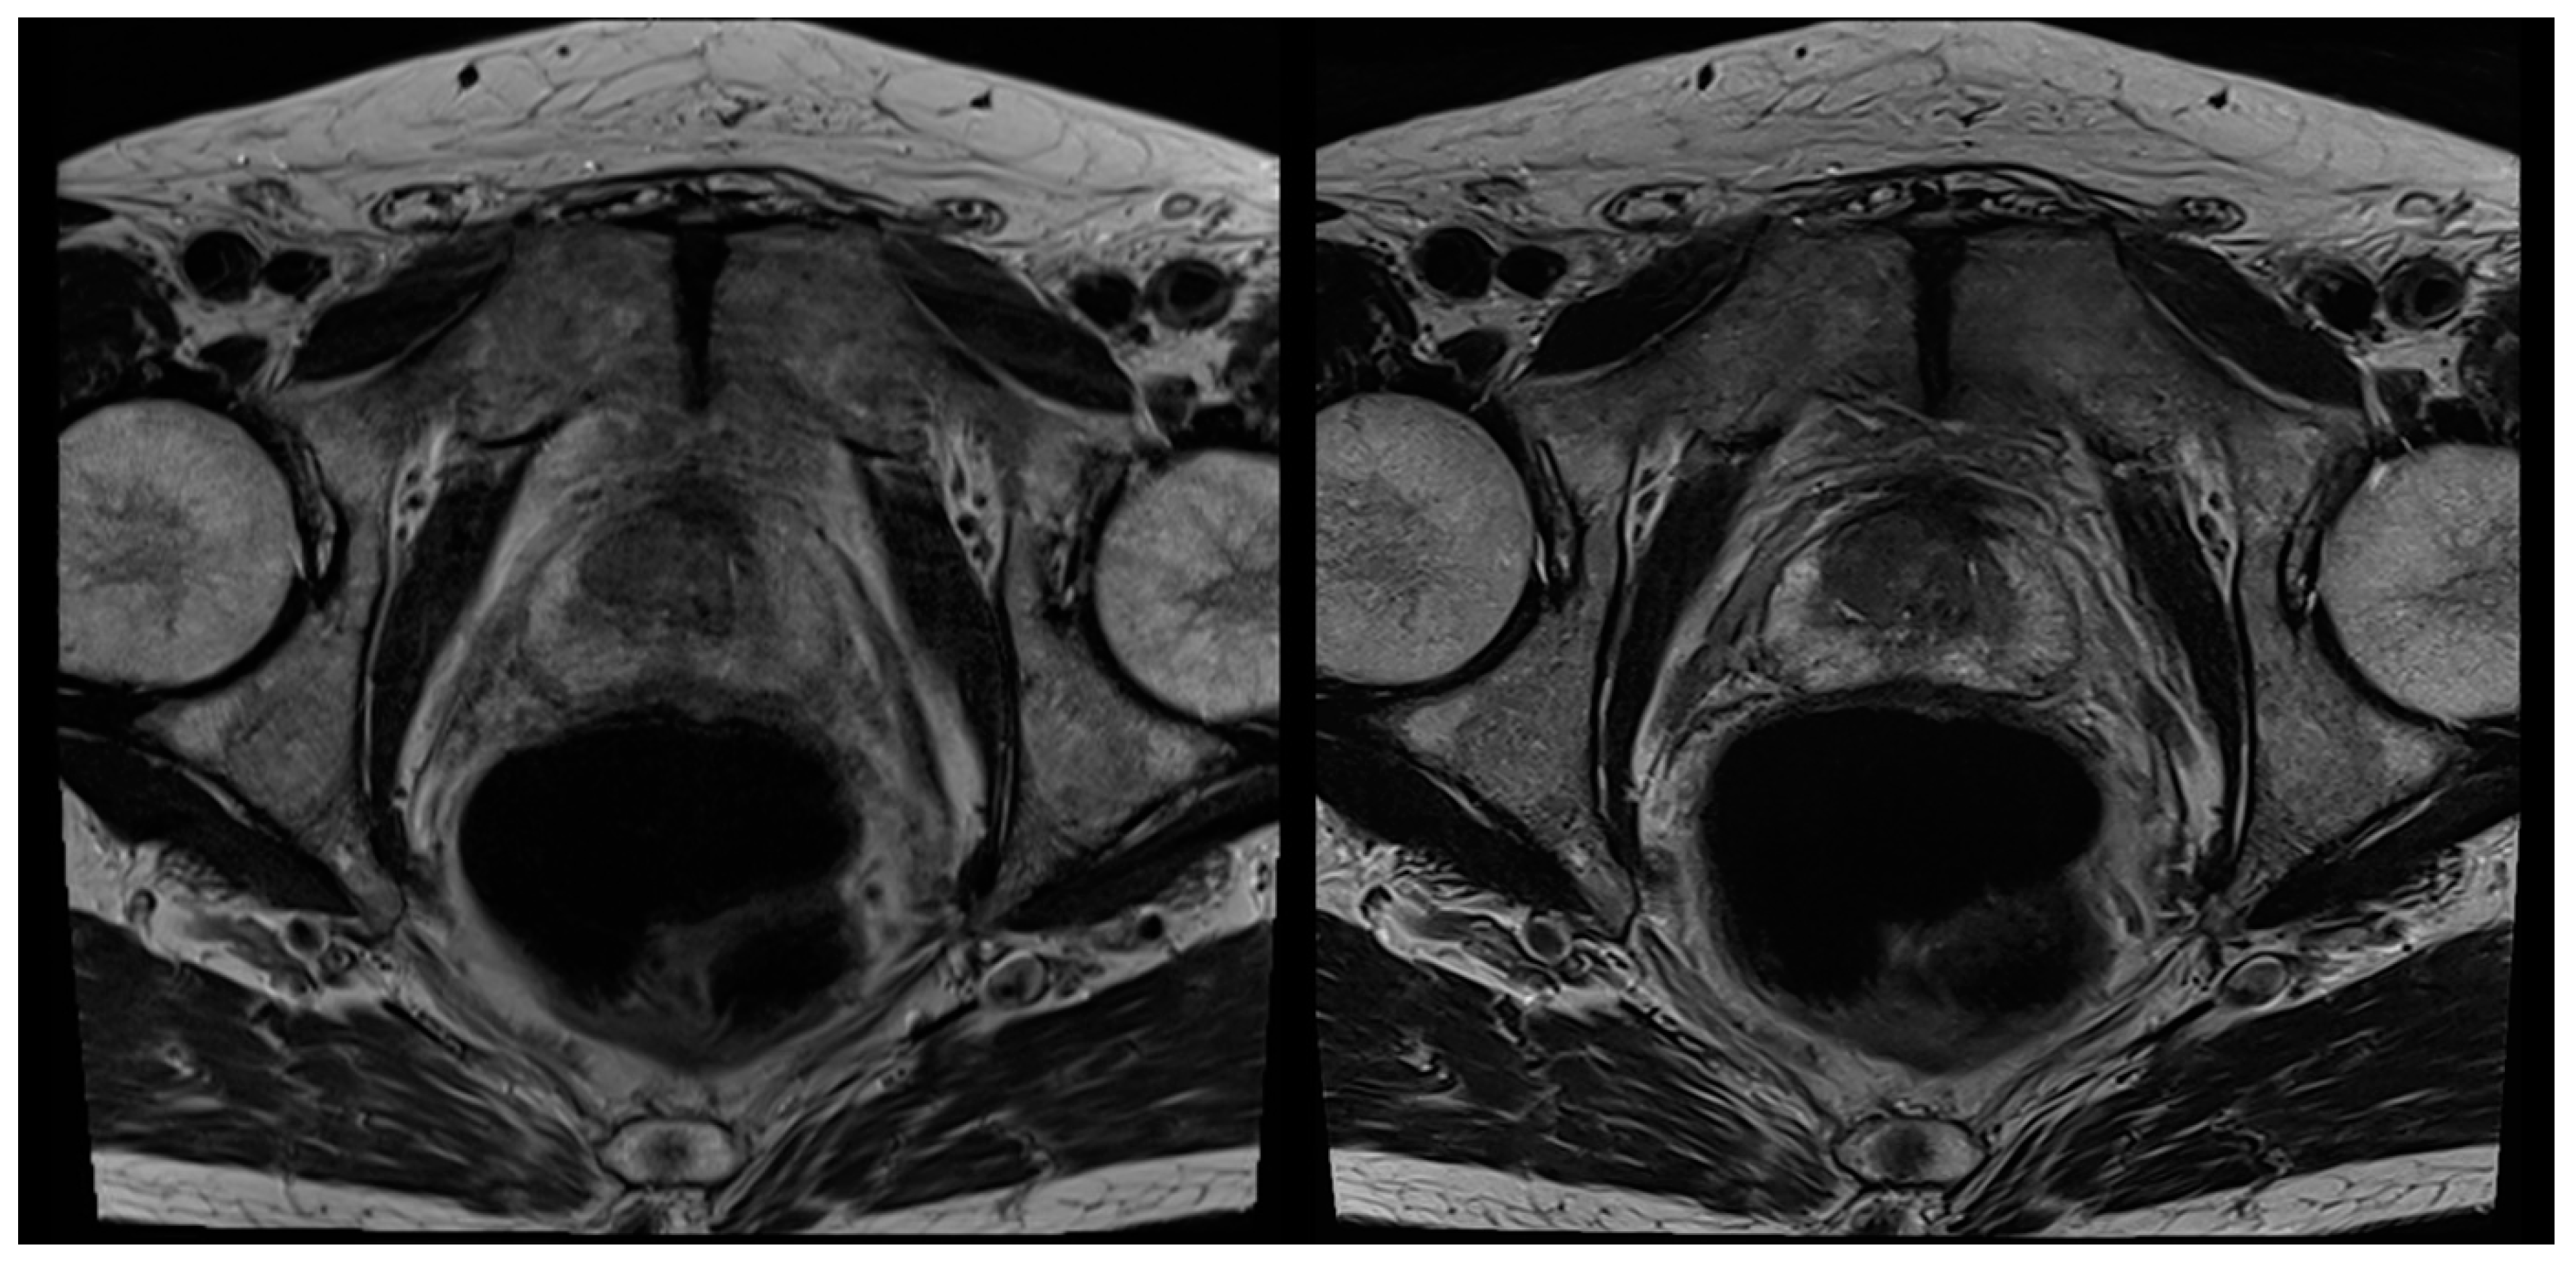

3.2. Evaluation of Qualitative Imaging Parameters

3.3. PI-RADS Scoring and Lesion Conspicuity

| Overall image quality axial | 3 (3–4) | 4 (4–4) | <0.001 | 3 (3–4) | 4 (4–4) | <0.001 |

| Overall image quality coronal | 3 (3–4) | 4 (4–4) | 0.002 | 3 (3–4) | 4 (4–4) | <0.001 |